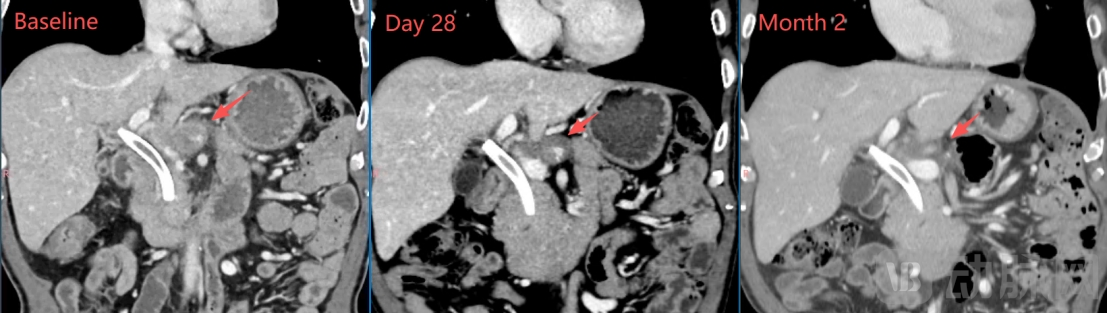

一个月的影像学检查显示:肝门区靶病灶明显缩小、肺部靶病灶基本完全消失,靶病灶直径之和从基线期的67mm缩小至43mm(下降35.8%),按RECIST1.1标准评估已达到部分缓解(PR);两个月的影像学检查显示:肿瘤病灶维持PR,且靶病灶直径之和进一步缩小至35mm(下降47.8%)。